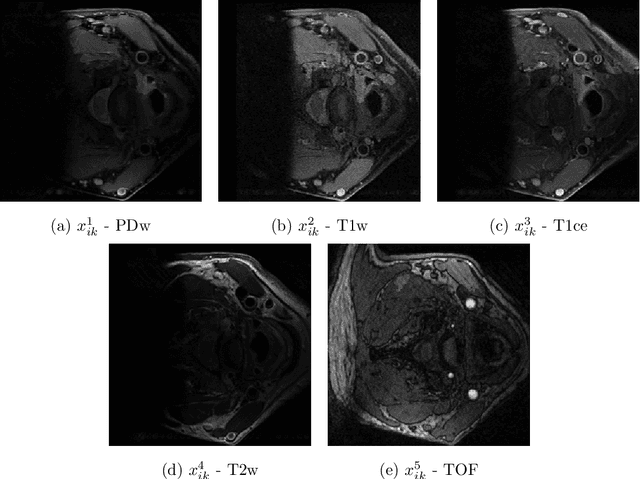

Abstract:The analysis of carotid arteries, particularly plaques, in multi-sequence Magnetic Resonance Imaging (MRI) data is crucial for assessing the risk of atherosclerosis and ischemic stroke. In order to evaluate metrics and radiomic features, quantifying the state of atherosclerosis, accurate segmentation is important. However, the complex morphology of plaques and the scarcity of labeled data poses significant challenges. In this work, we address these problems and propose a semi-supervised deep learning-based approach designed to effectively integrate multi-sequence MRI data for the segmentation of carotid artery vessel wall and plaque. The proposed algorithm consists of two networks: a coarse localization model identifies the region of interest guided by some prior knowledge on the position and number of carotid arteries, followed by a fine segmentation model for precise delineation of vessel walls and plaques. To effectively integrate complementary information across different MRI sequences, we investigate different fusion strategies and introduce a multi-level multi-sequence version of U-Net architecture. To address the challenges of limited labeled data and the complexity of carotid artery MRI, we propose a semi-supervised approach that enforces consistency under various input transformations. Our approach is evaluated on 52 patients with arteriosclerosis, each with five MRI sequences. Comprehensive experiments demonstrate the effectiveness of our approach and emphasize the role of fusion point selection in U-Net-based architectures. To validate the accuracy of our results, we also include an expert-based assessment of model performance. Our findings highlight the potential of fusion strategies and semi-supervised learning for improving carotid artery segmentation in data-limited MRI applications.